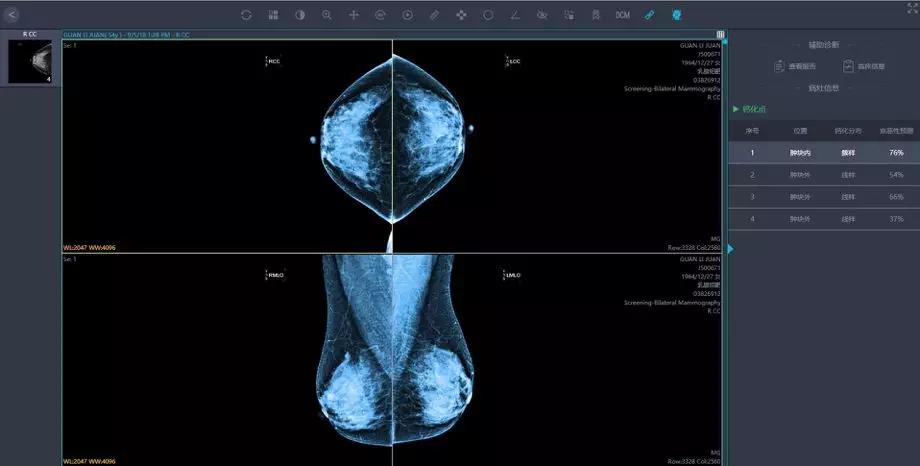

將這些影像學(xué)及臨床資料匯集,就為人工智能技術(shù)提供了大數(shù)據(jù)基礎(chǔ)。人工智能的影像識別和深度學(xué)習(xí)能力,能夠幫助醫(yī)生篩除正常影像,著重標(biāo)注疑似病灶的區(qū)域,讓影像科醫(yī)生審片更加精準(zhǔn)高效。

人工智能在影像識別的速度上勝于人工操作,同時也有利于臨床醫(yī)生制定針對性的治療方案, 特別對于偏遠(yuǎn)地區(qū)和基層醫(yī)生而言,這一技術(shù)的應(yīng)用更加意義重大。

英特爾技術(shù)團(tuán)隊(duì)和匯醫(yī)慧影緊密合作,幫助提升乳腺癌篩查的檢測精度和效率。將用于乳腺癌篩查的深度學(xué)習(xí)模型,應(yīng)用在英特爾至強(qiáng)可擴(kuò)展處理器平臺上,大幅度提升了數(shù)據(jù)的處理和推理效率,這得益于至強(qiáng)可擴(kuò)展處理器平臺的多數(shù)據(jù)流處理機(jī)制和對軟件框架的性能優(yōu)化:

針對來自多個醫(yī)療中心的海量影像數(shù)據(jù),英特爾至強(qiáng)服務(wù)器提供最高達(dá)768GB的超大內(nèi)存,配合多核心多線程處理能力,對乳腺采集影像進(jìn)行像素級別的特征識別,在紛紛擾擾的世界中尋找蛛絲馬跡,發(fā)現(xiàn)潛在問題。

匯醫(yī)慧影公司曾在胸部結(jié)節(jié),神經(jīng)系統(tǒng),甲狀腺等多器官系統(tǒng)影像與國內(nèi)外頂級醫(yī)院的影像及??漆t(yī)生進(jìn)行過人機(jī)讀片對比,經(jīng)過深度學(xué)習(xí)的人工智能系統(tǒng),讀片準(zhǔn)確率達(dá)到90%。

英特爾至強(qiáng)服務(wù)器可將深度網(wǎng)絡(luò)模型優(yōu)化并將數(shù)據(jù)集進(jìn)一步加強(qiáng),也將會繼續(xù)幫助提高該識別準(zhǔn)確率,其對數(shù)據(jù)的分析和比較“眼力”,早已突破人類極限,達(dá)到醫(yī)療影像辨識的新高度。